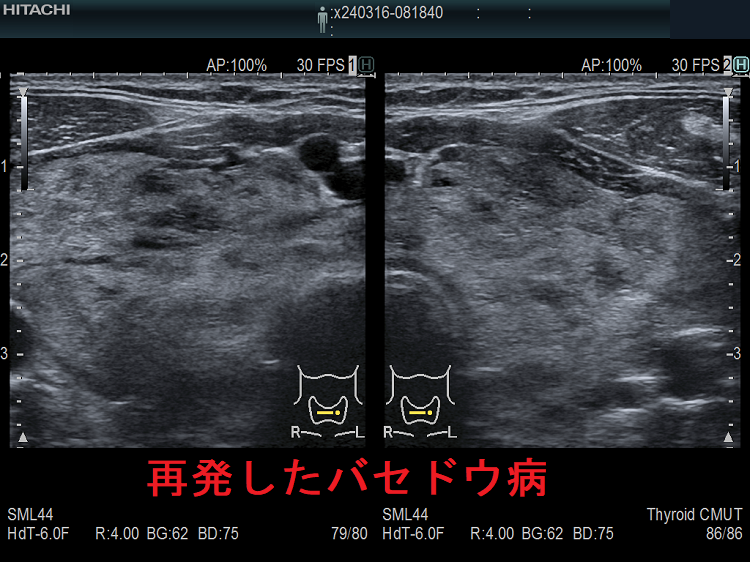

一般的な抗甲状腺薬の中止基準を用いてバセドウ病治療を中止後、再度甲状腺ホルモンが上昇して来たら、78%はバセドウ病の再発ですが、22%は一時的な甲状腺の破壊による無痛性甲状腺炎です(「上條甲状腺クリニックの甲状腺疾患Q&A」より)。

上條甲状腺クリニックの統計によると、バセドウ病/甲状腺機能亢進症の再発は、

- 1年以内再発62%

- 2年以内再発85%

- 3年以内再発92%

で、結局ほとんどが再発し、よくこんな中止基準を作ったものだと思います。

3年以上して再発しない人は、

- 平均11年そのまま寛解を維持

- 平均7年で3.3%再発

- 平均8年で3.7%甲状腺機能低下症に移行